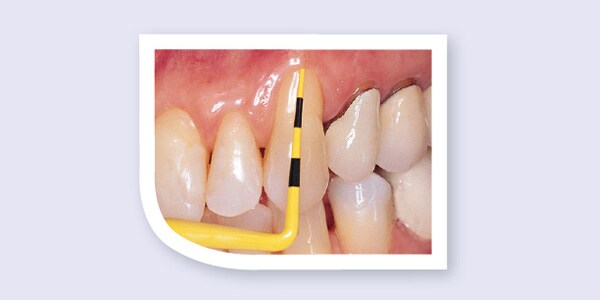

Compare the Colorvue probe to a standard metal probe. Colorvue's yellow tip with black markings provides superior contrast to the gingival tissue when measuring pocket depth.

5 mm of recession is easily assessed as a result of the excellent contrast between the Colorvue probe and exposed root surface. In addition, the Colorvue probe enhances measurement of periodontal attachment loss.